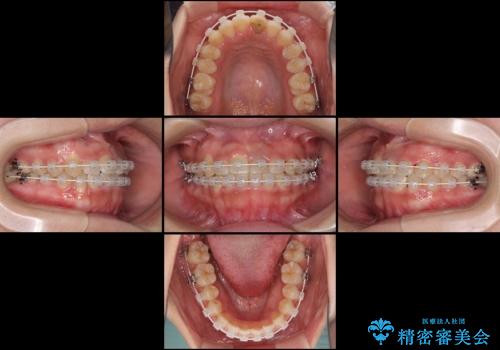

- 審美装置

マウスピース矯正の自己管理が面倒くさいことと、治療を早く終わらせたいとのことで、目立ちにくいワイヤー矯正にて歯列を整えることとしました。

1年半はかかると思っていた治療期間ですが、反対咬合となっている前歯が思いの外早く動き、僅か9ヶ月で終了させることができました。

前歯を気にせず笑えるようになり、患者様には大変満足していただきました。